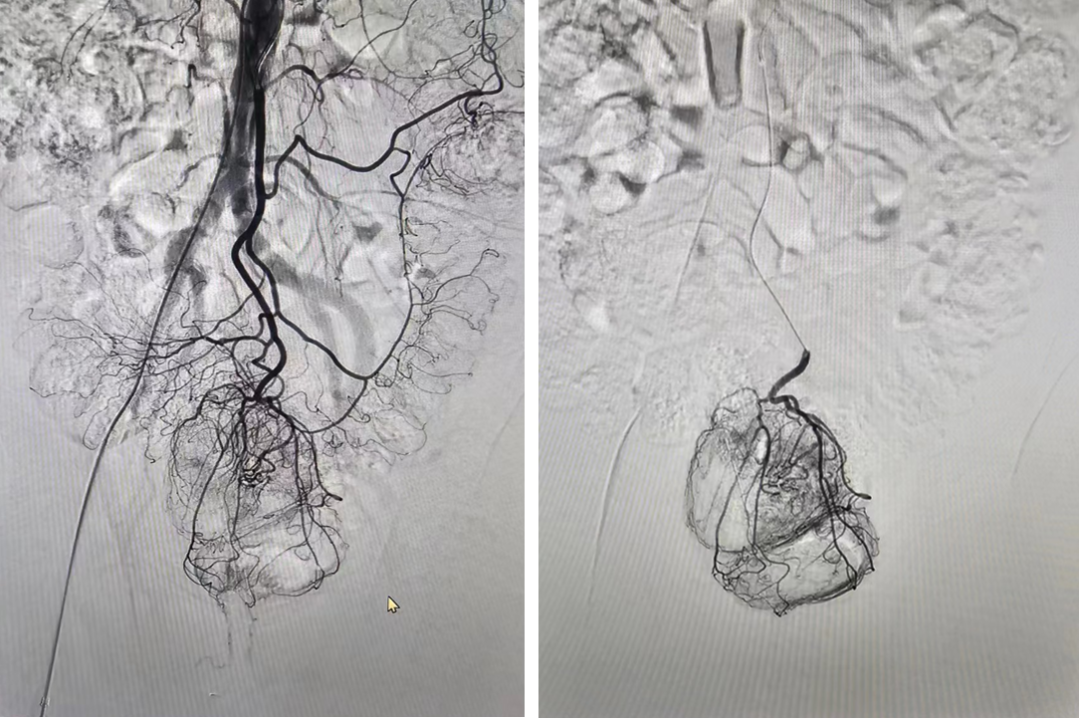

痔疮出血:不容忽视的介入新领域

痔疮是最常见的肛肠疾病,其引发的出血量巨大。通过超选择性栓塞直肠上动脉等分支,可有效控制出血,为药物治疗无效的患者提供微创解决方案。

图:痔疮出血(引自苏大附二院介入科)